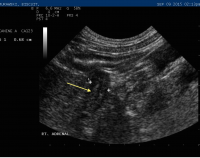

post adrenalectomy